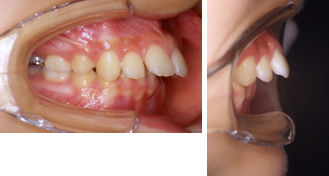

上顎前突(出っ歯)10歳男子

治療前

出っ歯治療後

※この治療には個人差があります

①主訴:出っ歯を治したい

②診断名あるいは主な症状:上顎前歯の前方への突出

③年齢:10歳

④治療に用いた主な装置:ライトワイヤー +(機能的矯正装置)

⑤抜歯部位:非抜歯

⑥治療期間:約1年半~2年

⑦治療費:検査:38,500円

基本矯正費用:440,000円~

調整料:6,600円 (ひと月に1回)

⑧リスクと副作用:治療開始後数日は噛むときに痛みがあります。

虫歯予防のため適切な歯磨きが必要

装置が破損することがあるため、その時は連絡をすること

後戻り防止のため、保定装置の装着が必要である。

第2期(永久歯列期)での仕上げの治療が必要になる場合もある